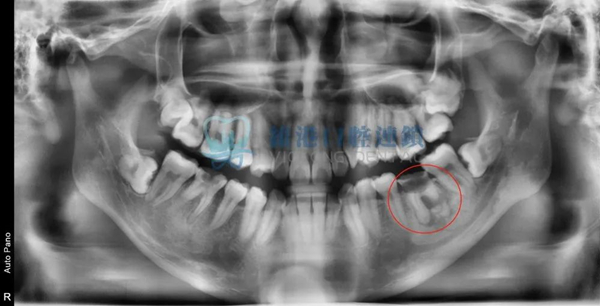

嚴重案例

頜面囊腫波及根尖